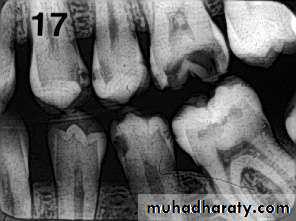

PIT & FISSURE CARIES

Incipient occlusal lesions:Not very effective.

Caries starts on the walls

of the pits & fissures and

tends to spread

perpendicular to the DEJ

Only detectable change is

a fine gray shadow at the

DEJ.

Moderate occlusal lesions:

Moderate occlusal lesions: First to induce specific changes

helping in a definitive diagnosis

Broad based, thin radiolucent

zone in dentin with minimal or

no changes in enamel

Presence of a band of increased

opacity between the lesion and

the pulp chamber due to

calcification within primary

dentin

This feature is not seen in

buccal caries

Severe occlusal lesions:

Readily observed bothclinically and

radiographically

Appear as large cavities in

the crowns of the teeth

However pulp exposure

cannot be determined

Incipient occlusal lesions

Moderate occlusal lesionsSevere occlusal lesions